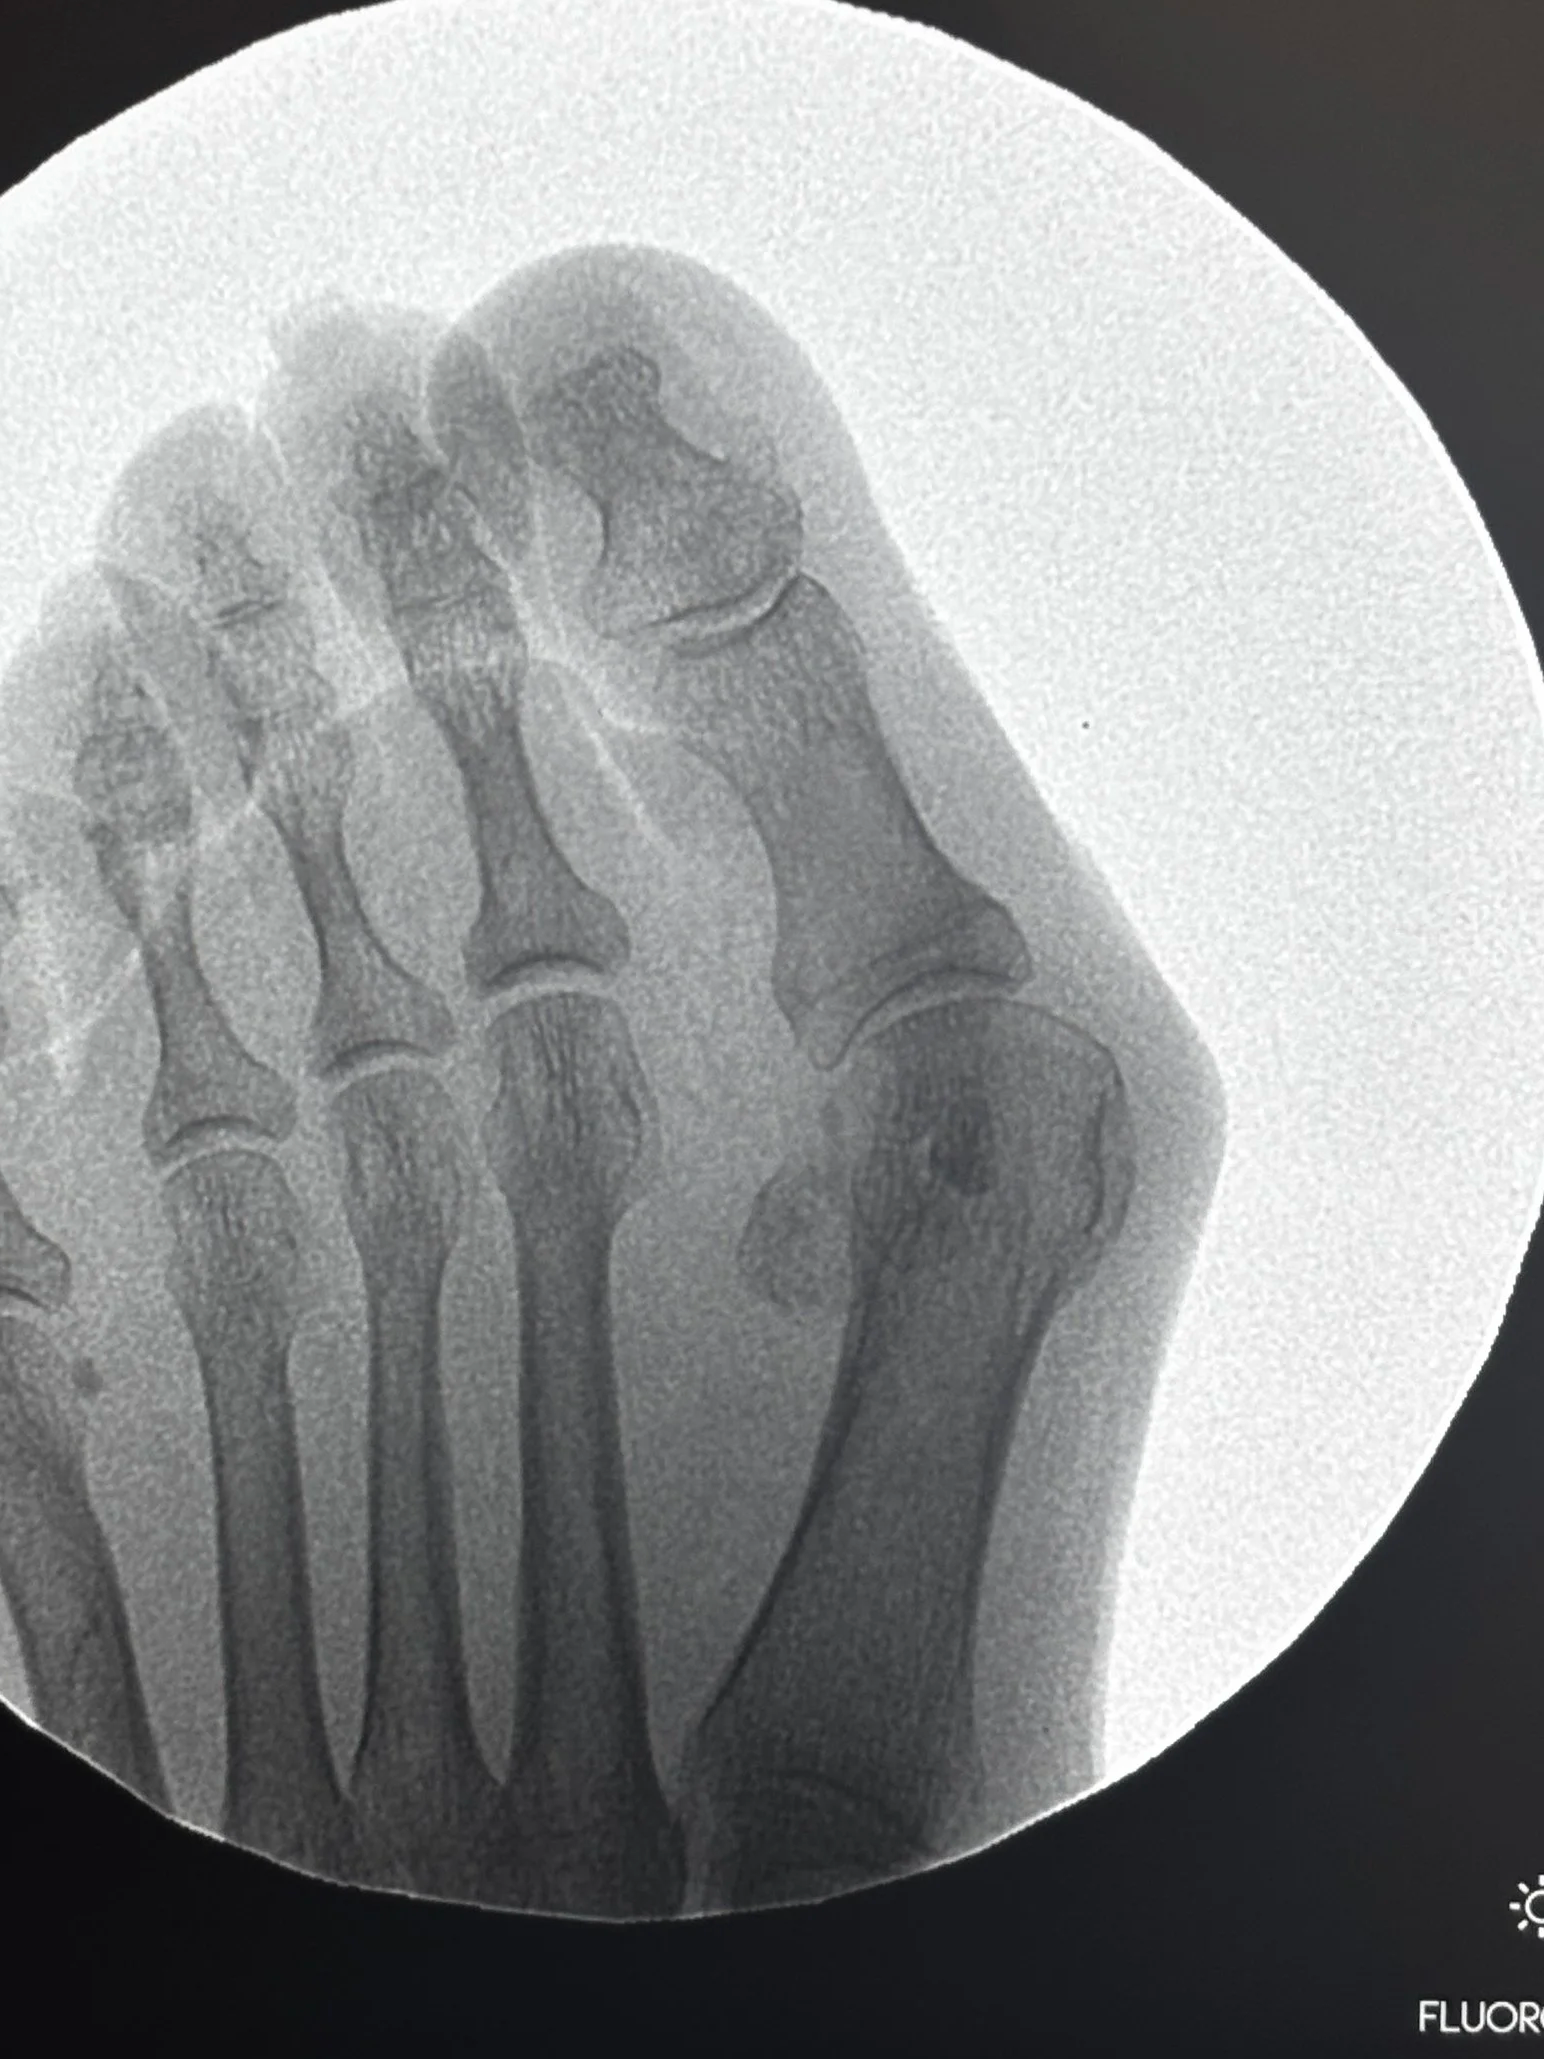

Resultado: antes y después

En estas fotos podemos observar el antes en 1ª y 2ª foto, el día de la intervención 3ª foto, y en el cambio de vendaje de 3ª semana tras intervención.

El resultado muestra no solo una mejora estética, sino también funcional: